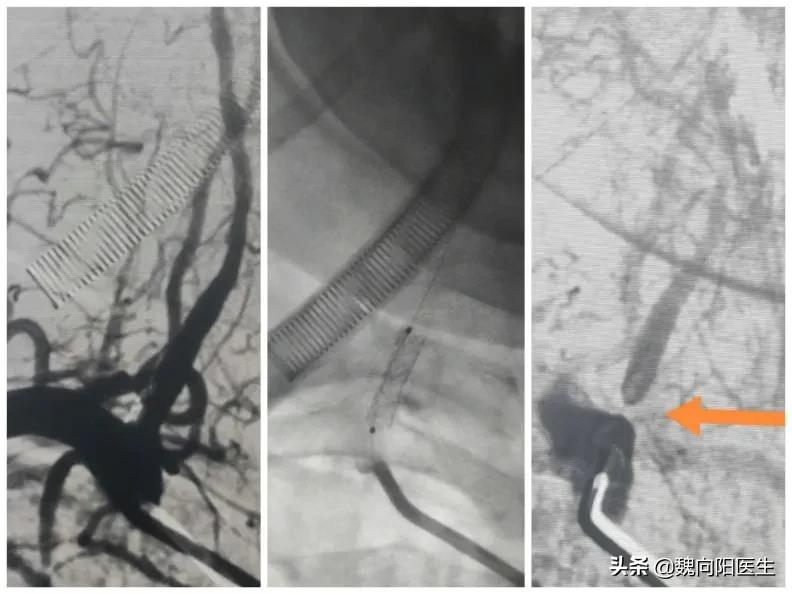

患者转入病房后,医护已经做好溶栓前准备,在最快的时间内给予患者输入溶栓药物rt-PA(0.9mg/KG)。考虑患者脑梗死是由于大动脉闭塞导致的,医生建议患者立即行脑血管造影检查,但是患者老伴儿好像并没有认识到问题的严重性,只说需要打电话考虑一下,然后就在那默默的呆着。时间一点一点过去了,大约1小时后,医生只能再次反复的跟患者的老伴沟通:现在患者没有时间再等了,随着缺血的时间延长,越来越多的脑细胞在因缺血坏死,因此需要患者家属马上做决定。经过医生反反复复的催促患者老伴,才最终给患者姐姐打了一通电话,同意手术治疗。12:00终于把患者推进了导管室,在做脑血管造影过程中患者躁动明显,处于严重不配合状态,只能立即联系麻醉师,给予全麻。患者安静下来后立即做脑血管造影发现左侧椎动脉闭塞,右侧椎动脉是一个次全闭塞状态,狭窄的只剩下一根头发丝粗细的血管腔,颅内血供出院严重不足状态。给予植入一根血管支架后,立即恢复颅内的血供。手术做的很顺利,为了配合治疗,防止患者醒后再次躁动,保持患者镇静状态返回病房。